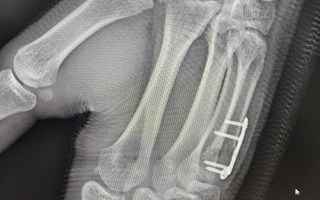

Nam sinh gãy xương bàn tay sau cú đấm boxing

(NLĐO) - Sau cú đấm khi chơi boxing, nam sinh 17 tuổi chủ quan bỏ qua cơn đau tay. Hai tuần sau nhập viện, bác sĩ phát hiện bệnh nhân gãy xương bàn tay.